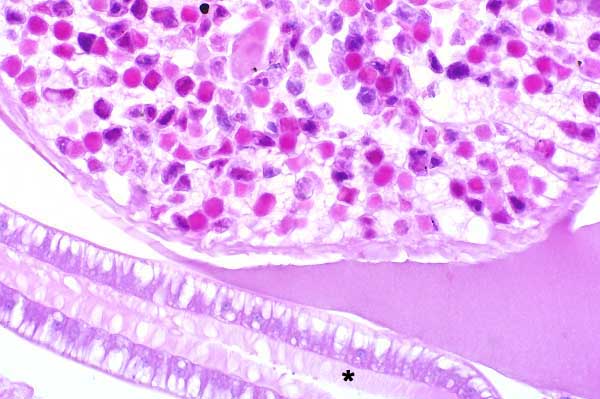

Digestive tract is lined by many uninucleate columnar epithelial cells with long, prominent microvilli (brush border)(*).